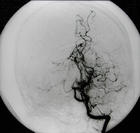

烟雾病又名脑底异常血管网,是一组以颈内动脉虹吸部及大脑前、中动脉起始部狭窄或闭塞,脑底出现异

常的小血管网为特点的脑血管病。因脑血管造影时呈现许多密集成堆的小血管影,似吸烟时吐出的烟雾,故名烟雾病。

脑血管造影可以发现颈内动脉起始部、大脑前、中动脉起始段狭窄或不显影,基底节区可见大量细小血管团如吸烟吐出的烟雾。此外可见脑内形成侧支循环代偿支。随着病程的延长,代偿吻合支的数量逐渐减少或缩小。

5.脑血管造影 见颈内动脉虹吸上段和大脑前、中动脉起始部狭窄,脑底烟雾状异常血管网和广泛的侧支循环形成。应与脑动脉硬化性脑梗死和动静脉畸形鉴别。